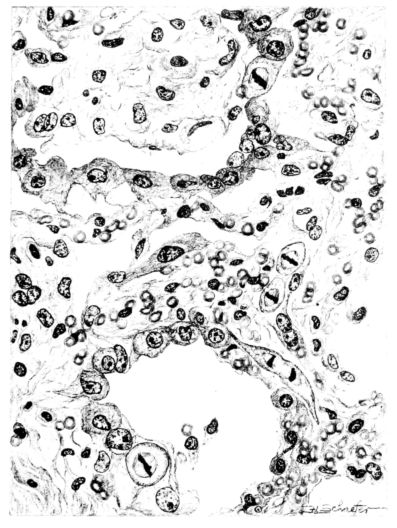

FIG. II. AUTOPSY NO. 98. DRAWING OF A SECTION THROUGH A TRACHEA SHOWING NECROTIZING HEMORRHAGIC INFLAMMATORY PROCESS OF THE MUCOSA.

The changes are less marked, perhaps, in the trachea than in its finer ramifications. The mucosa is constantly more or less destroyed and large areas, usually focal, are entirely devoid of their epithelial covering. This is replaced by a sparse exudate, composed largely of red blood cells, mucus, a small amount of fibrin, and nuclear fragments (Fig. II). It may dip into the submucosa for a short distance, but usually these indentures are associated with the ducts of the mucous glands into which the inflammatory reaction extends. A more striking feature than the exudate, however, is the edema and the congestion of the submucosa. The loose areolar tissue of the submucosa is spread widely apart, and throughout it distended blood vessels are very conspicuous. Occasionally such a vessel is broken and actual hemorrhage appears in the submucosa. Occasionally, too, the inflammation extends down the duct to the mucous gland itself, and here, also, aplastic inflammatory reaction is evident, inasmuch as the acini now stain intensely red with the cells undifferentiated from each other and specked here and there by broken remains of the dead nuclei (Fig. III). After the disease has continued for a short period, even at the end of five or six days, some regeneration of the epithelial lining may be seen (3) (Fig. IV). But despite this, the acute picture persists, and there goes on, side by side, an attempted repair characterized by epithelial regeneration and the same evidence of acute change. Since the lesion is essentially a superficial one, scars or contractures of any extent are not encountered in the trachea, even in examples of the disease that have ended fatally only after many weeks.[4]